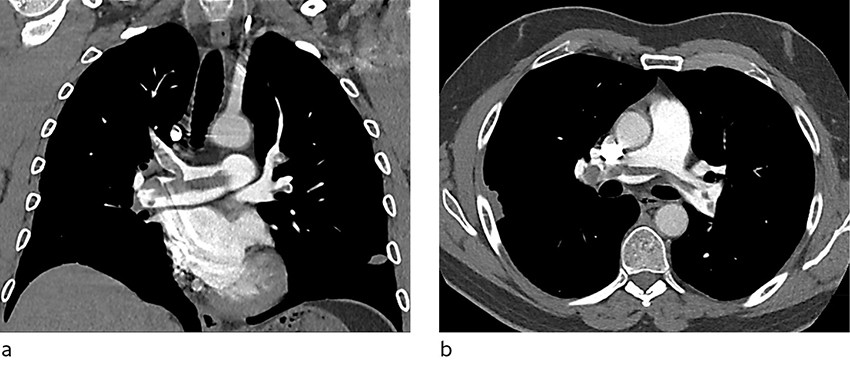

Enoksaparin (Klexane) 1 mg/kg ble gitt subkutant × 2. Pasienten ble lagt på telemetriovervåking, og CT av lungearterier ble bestilt til dagen etter. Denne avdekket en omfattende sadeltrombe samt bilaterale segmentale lungeemboluser (figur 1). Pasienten ble derfor flyttet til medisinsk intermediær avdeling for tett overvåking av sirkulasjonsstatus. Ekkokardiografi påviste en trombe i pulmonalarterien, lett dilatert høyre ventrikkel og avflatning av det interventrikulære septum. Estimert systolisk lungearterietrykk var 55 mm Hg (< 36).